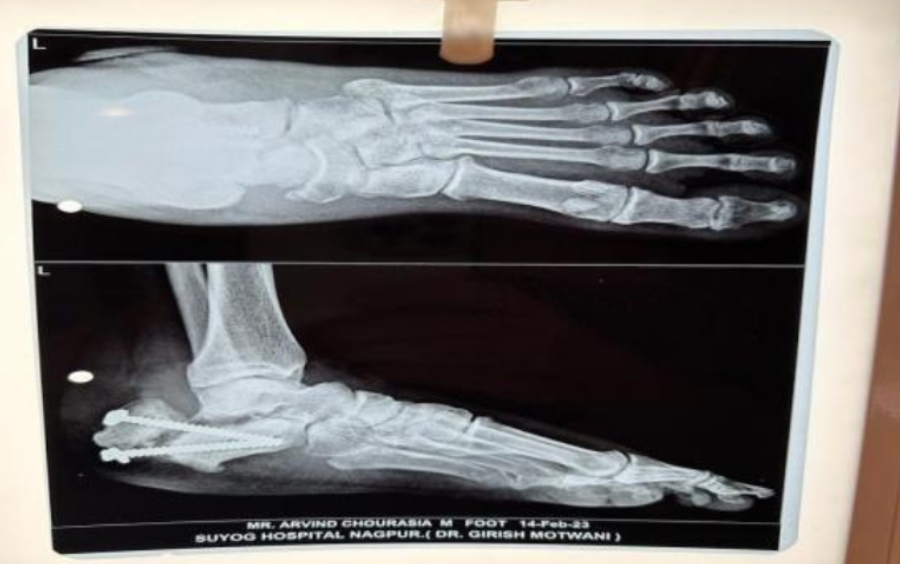

The Patient’s Case Presentation The patient had undergone closed reduction and internal fixation for a one-year-old left calcaneum bone fracture. Regretfully, he had persistent osteomyelitis of the calcaneum as a result of an infection at the surgery site. The illness remained after six months of conservative treatment, requiring another course of action.

Line of Treatment Dr. Girish Motwani used a two-phase therapeutic strategy. Read more